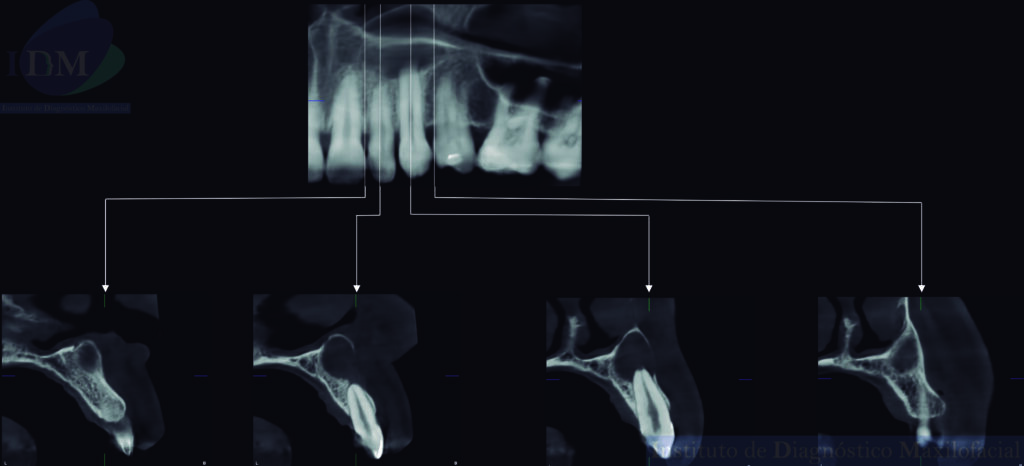

A la evaluación de la tomografía volumétrica (CBCT) en los cortes axiales (Figura 2) y transaxiales (Figura 3), se aprecia imagen isodensa unilocular que se extiende en sentido cefálico caudal desde piso de fosa nasal izquierda hasta tercio apical de piezas 22 y 23, en sentido mesio distal desde distal de pieza 21 hasta mesial de pieza 24, que ocasiona borramiento parcial de la lámina dura de piezas 22 y 23, adelgazamiento del piso de fosa nasal izquierda; adelgazamiento, expansión y erosión parcial de la tabla ósea vestibular.

CORTES TRANSAXIALES